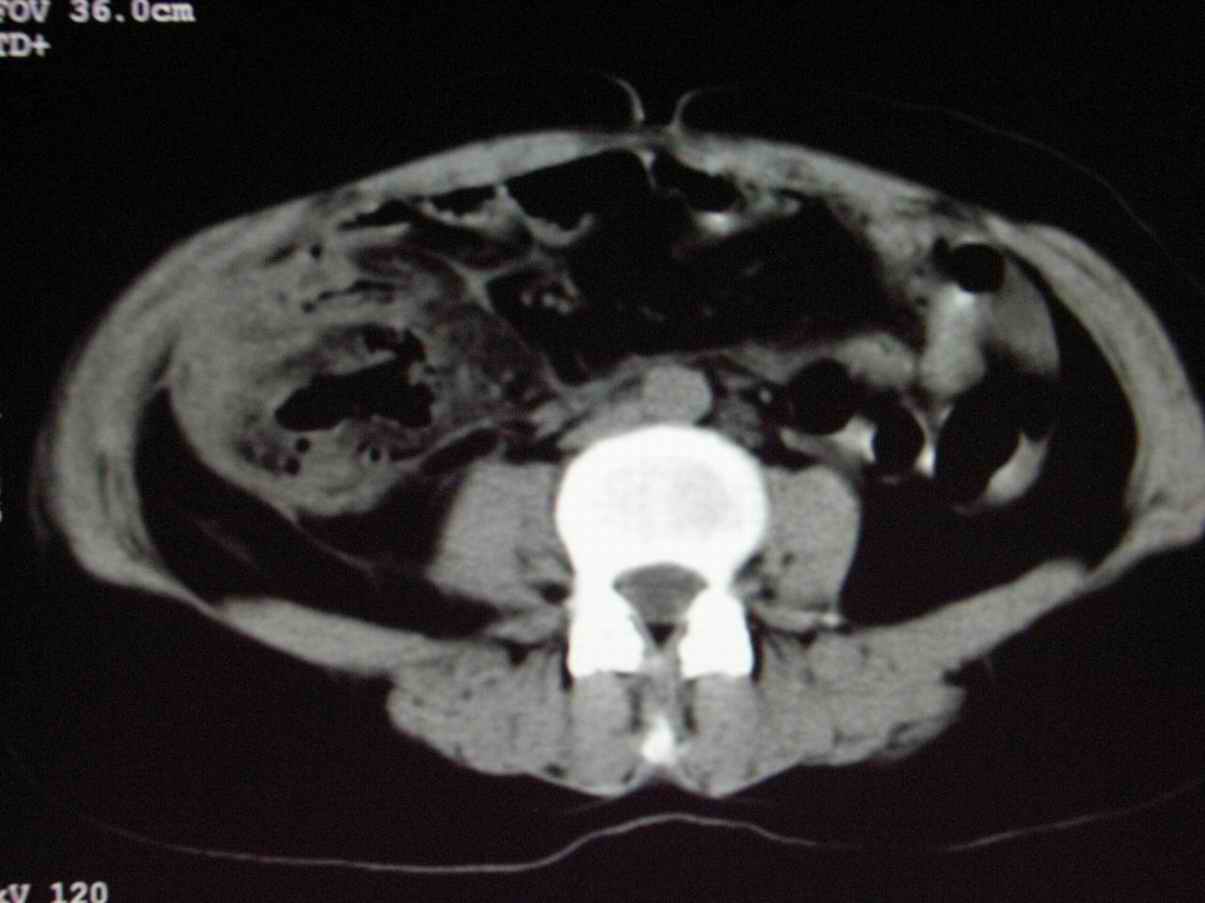

男;67岁,腹胀,腹痛,便血半年;钡餐透视发现右下腹部占位性病变

ct表现;病灶成环状软组织肿块,表现为不对称的肠壁增厚;肠腔变型.

升结肠肠壁不均匀增厚,肠腔变形,支持结肠癌.